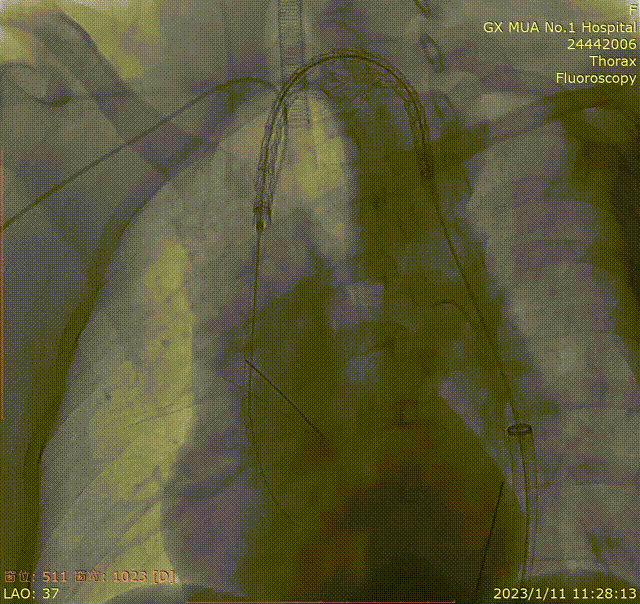

双导丝置入长鞘过弓

第一导丝用于平滑弓形角度,并稳定血管形态,第二导丝保持长鞘的前进方向与前者同轴。

即使有双导丝加持,长鞘在过弓的时候还是会遇到阻力,此时不要蛮力推进,可以轻微抖动回撤导丝,卸除一部分应力再尝试推进,切勿追求一步到位。

引导鞘过弓

推送主体于目标锚定区更前端定位造影

支架输送系统塑型至弓部导丝支撑完成支架输送前置于LCCA前,将引导鞘退至降主。